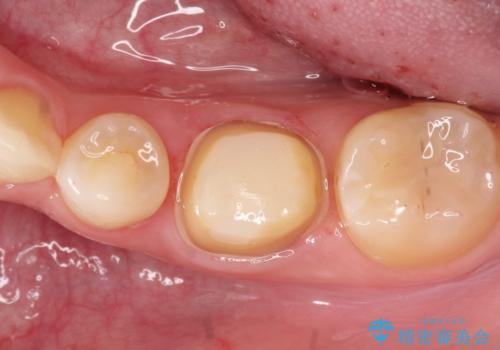

【セラミッククラウン】適合の悪いアンレーのやり替え

- 過去に他院で治療された奥歯が気になりご来院されました。

セラミッククラウンによる治療を希望されていたため根管治療から処置を行っています。